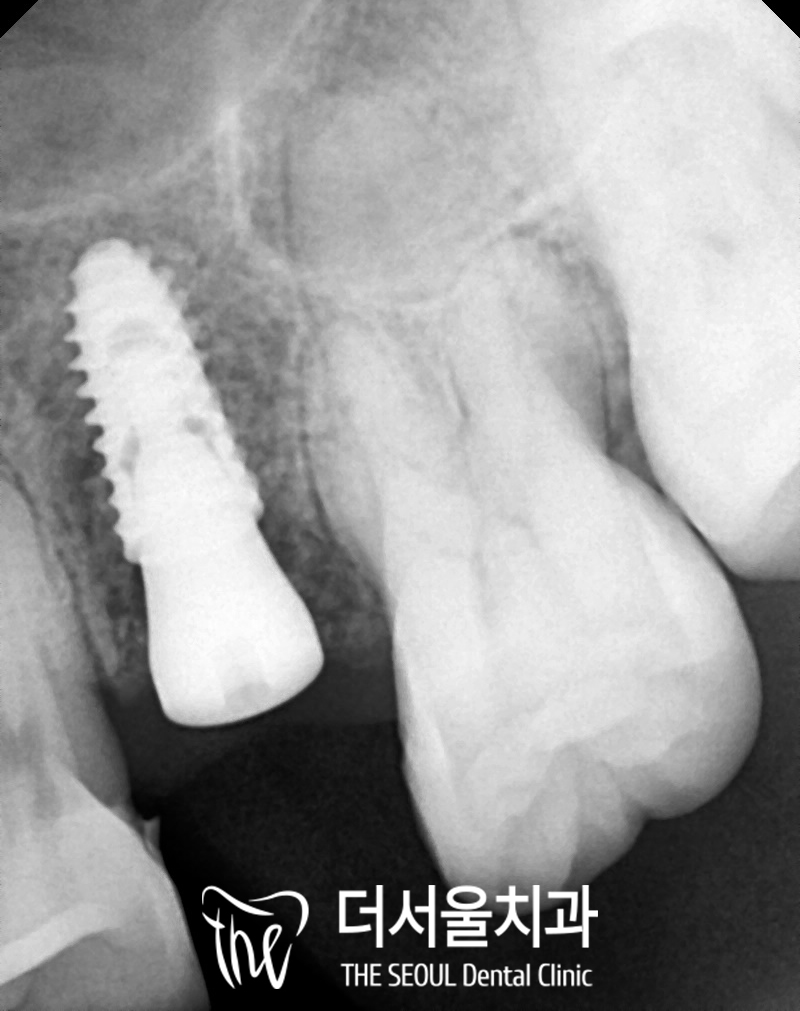

상하악의 해부학적 구조를 피해

안전하게 식립을 마친 모습입니다.

주변으로 하얗게 치조골이

잘 차올랐다면